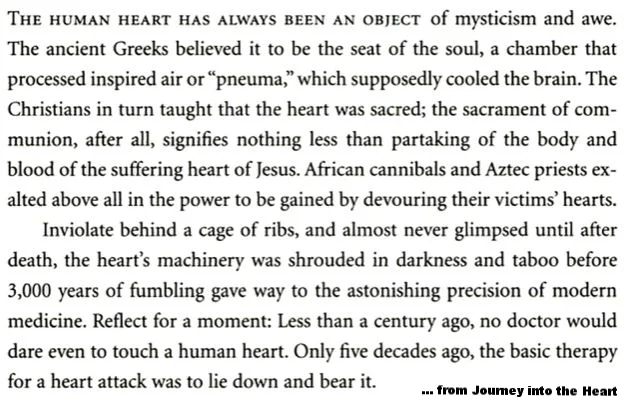

The Nobel Prize in Physiology or Medicine 1924 ... awarded to Willem Einthoven: In regard to Einthoven’s work, Professor J.E. Johansson, Chairman of the Nobel Committee for Physiology or Medicine of the Royal Caroline Institute, made the following statement:

“The Staff of Professors of the Royal Caroline Institute has on 23rd October, 1924, decided to confer this year’s Nobel Prize in Physiology or Medicine to the Professor of Physiology at the University of Leiden, Willem Einthoven, for his discovery of the mechanism of the electrocardiogram.

“Einthoven’s name is linked partly with the design of a physical instrument, the string galvanometer, partly with the so-called electrocardiogram, a record of the electrical potential fluctuations at the surface of the body, which accompany the heart beat. The heart beat, like the piston movement of a steam engine, is a cyclic process. Behind this process lies, in the first place, a similarly cyclic process in the heart muscle.

…

“The same mechanism governing the characteristics of the electrocardiogram, also governs the characteristics of the mechanical process during the heart beat. We should remember in this connection that the mechanical process not only consists of the succession of the stimulation of the separate parts of the heart compartments, but also of the cooperation of the individual parts of the heart wall which form the essential condition for the mechanical effect in the individual ventricle or in the individual auricle. A deficiency in this cooperation can, with regard to the mechanical effect, be as fatal as a valvular insufficiency. Today, the importance of the mechanism discovered by Einthoven can easily be realized.”

Paul Dudley White: The Father of American Cardiology*

History of Cardiology @ Massachusetts General Hospital

100 Years of Cardiology at MGH - AHA News article 12/6/16